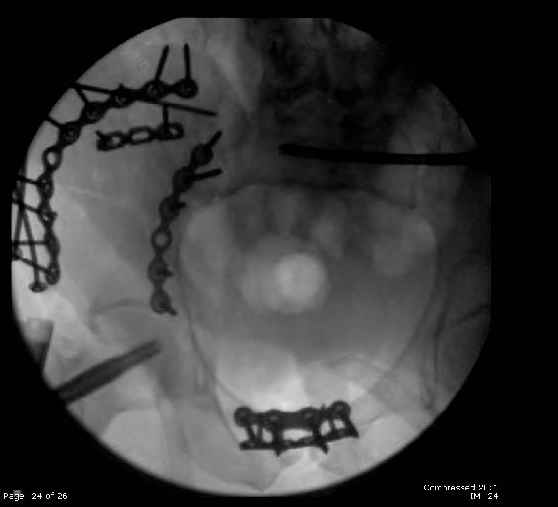

Here are the postop fluoros.

First exposed symphysis & clamped w/Faraboeuf as close to anatomic as possible.

Then extended to R ilioinguinal,really just the lateral window.

Reduced the triangular wedge piece of iliac wing to posterior intact ilium (crescent), held w/k-wire, then used 3-hole push plate to keep from moving, lagged from lat-med w 3.5 screw.

Then 6-hole plate along brim with 1 screw in R sacral ala. Then lagged 2 screws along crest A --> P. finally 10-hole plate along inner aspect of crest. R posterior ilium still a bit stepped off.

Symphysis then 'fine-tuned' & reduced as close as possible to anatomic (but, still with forward rotation of R hemipelvis - or, is it extension?) Accepted that amount of deformity and plated symph

with 4-hole symphyseal plate.

Fluoroed L SI joint and it seemed stable, but wide. So, applied c-clamp to try to squeeze down L SI joint (and note, on the last slide attached, that it's still wide), and got it closer. Single perc Iliosacral screw 40mm thread.

Applied second plate anteriorly on symphysis as I wasn't confident L SI was as stable as it could be and wanted to protect it better.

Thoughts? Thanks for the advice, it's appreciated.

Jeff